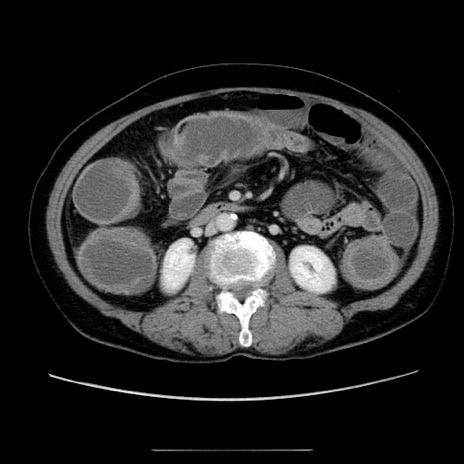

症例5(横断像)

【症例】70歳代女性

【主訴】お腹が張る

【現病歴】1週間くらい前から腹部膨満の自覚あり。昨日夜から増悪したため、本日救急外来受診。

【身体所見】意識清明、BT 36.5℃、BP 165/106mmHg、HR 80bpm、SpO2 98%、腹部:膨満、軟、自発痛・圧痛なし、触診にて不快感あり、腸蠕動音:減弱

【データ】WBC 12600、CRP 1.04